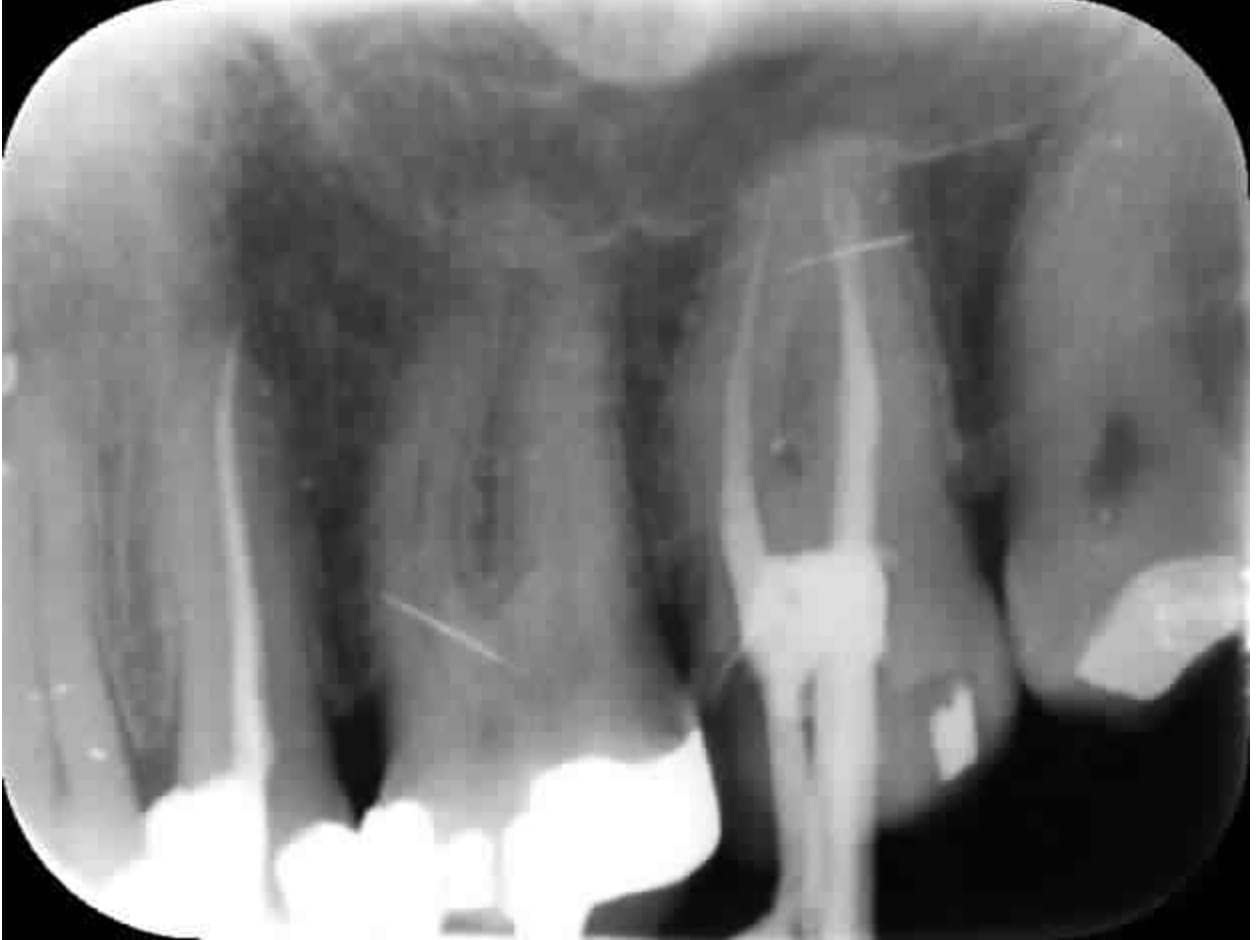

Figurez vous que j'ai eu le meme problème que notre confrère avec cette 27. Endo réalisée 7 ans auparavant. L'enfoiré de correspondant a dit qu'il y avait un problème alors que le patient ne sentait rien.

Capture d écran 2019 08 28 11.07 - Eugenol